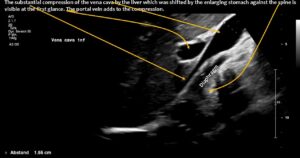

Normal size of the superior mesenteric vein which is slightly slimmer than the superior mesenteric artery as long as the patient was fasting. However, due to the limited space in the flat upper abdomen the superior mesenteric artery already is shifted to the left side of the aorta instead of lying precisely in front of it.

Here, the unique mechanism causing compression of the duodenum by the enlarged superior mesenteric vein is demonstrated. In contrast to conventional SMA syndrome, the superior mesenteric vein acts as a pillar against which the aorta presses, thus obstructing the duodenum. It is important to be aware of the variability in the position of the superior mesenteric artery in patients with a flat abdominal cavity. When the stomach is full, it may shift further to the left (or right) of the SMA than in the fasting position.